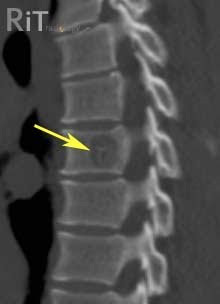

Если на теле более трёх поверхностных образований, то вероятность того, что они есть и внутри велика. Таким пациентам проводят МРТ и КТ, исключая опухоль печени, головного мозга, костей, а также системное заболевание, симптомом которого бывает кавернома.

Применяют в труднодоступных местах (позвоночник) при отсутствии других способов повлиять на заболевание. Проводят лучевое лечение курсами. Показывает массу осложнений, небезопасно.